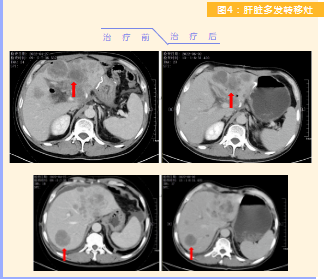

患者完成1周期治療后,上腹部疼痛癥狀基本消失,梗阻性黃疸癥狀緩解,腫瘤指標(biāo)下降(圖1),肺部多發(fā)轉(zhuǎn)移灶消失和縮?。▓D2),雙肺門淋巴結(jié)縮?。▓D3),肝臟多發(fā)轉(zhuǎn)移灶縮?。▓D4)。